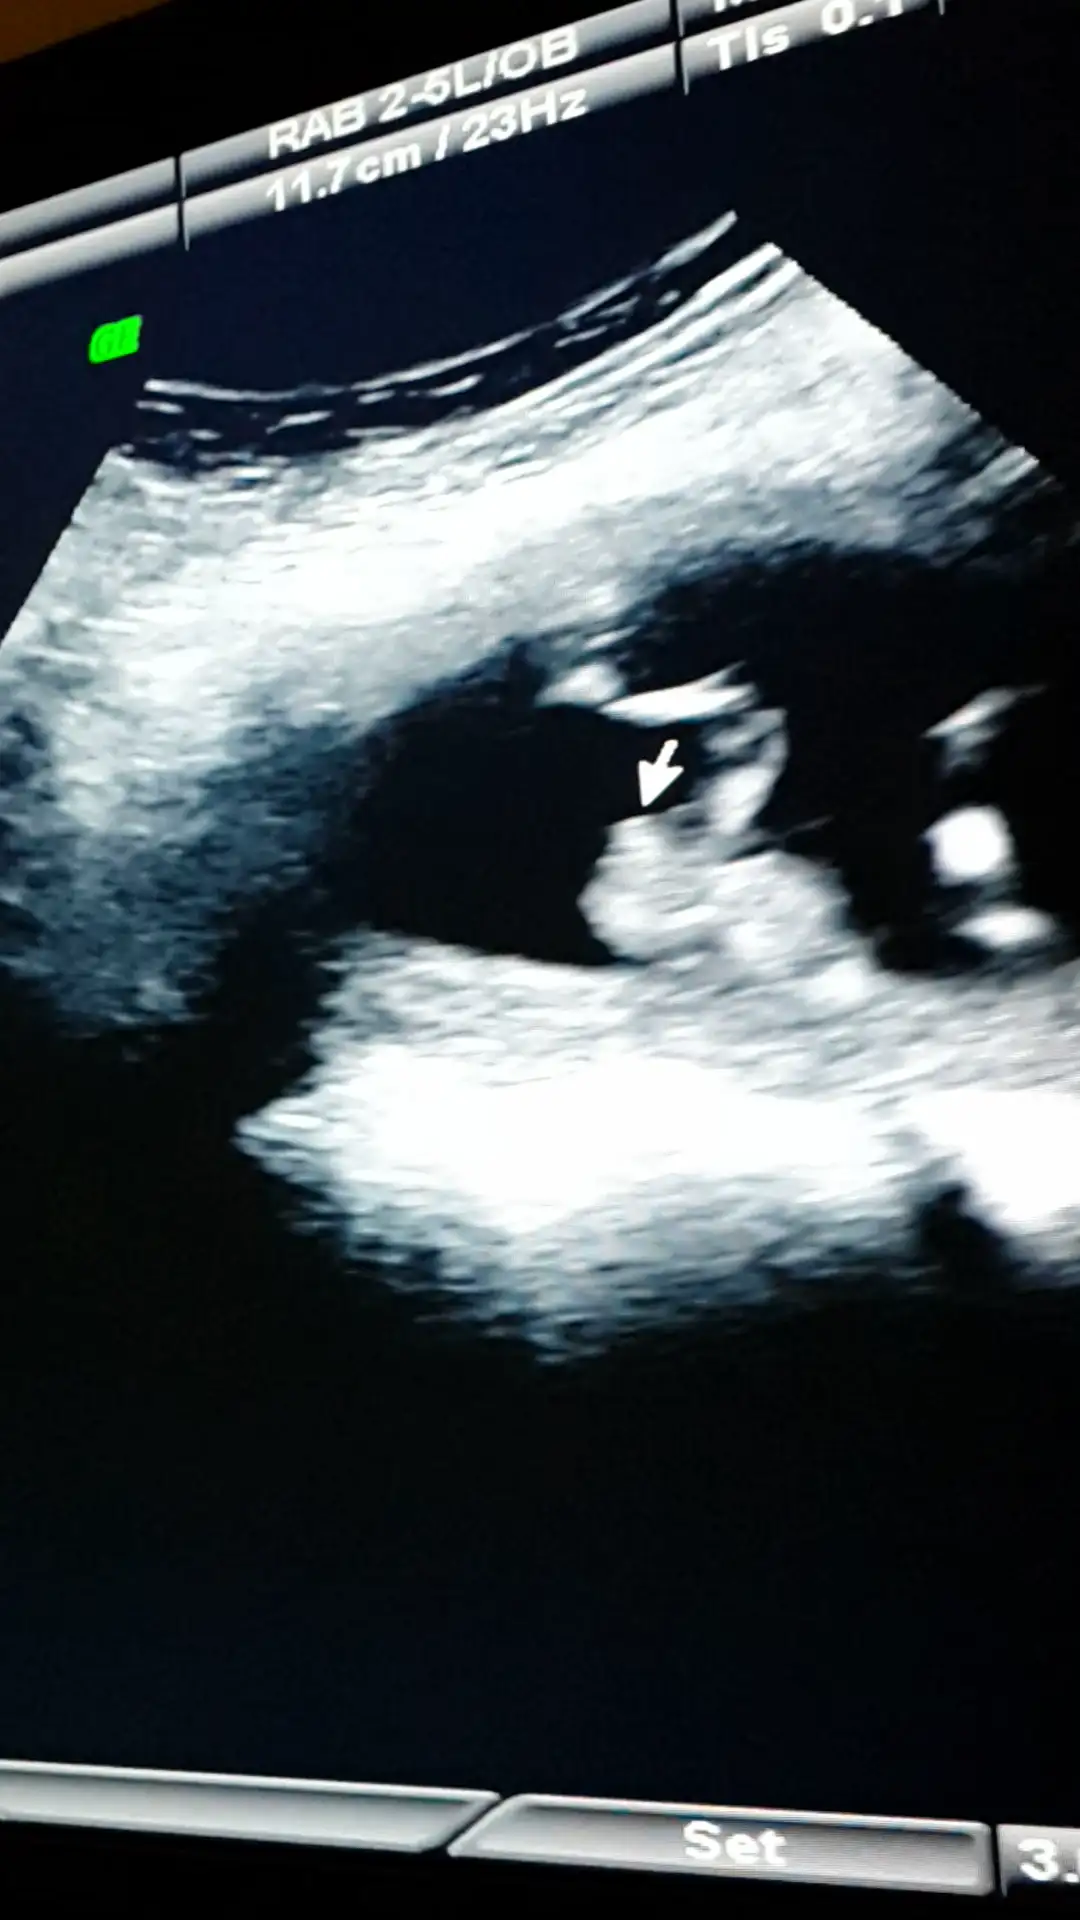

Canim resmini nub teorisi sayfasinda paylasayim bakalim ne dicekler orkidemde orda gorurse cvp verir haber ederimdenizkinub7 .!.:Canim esim bebisi videoya cekmisti ordan kopyaladigim bir resmi ekledim doktorun tam cikintisini isaretleyip gosterdigi yerin resmi. Onuda paylasmak istedim bi bakarsin tekrar doktorla ayni fikirdemisiniz merak ettim senin yorumunudaEki Görüntüle 1311947 Eki Görüntüle 1311948 Eki Görüntüle 1311949